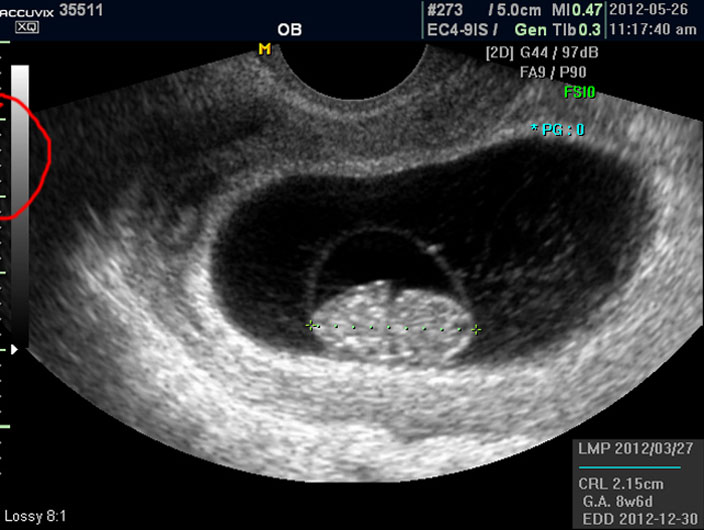

상기 이미지는 정지 이미지이기 때문에 심장 움직임과 같은 것은 설명해 드리지 못했지만 이 시기에 중요하게 확인해야 할 점의 하나는 심장 박동의 유무와 횟수입니다.

태아의 심장 박동은 성인보다는 매우 빨라서 보통 분당 120회에서 160 정도 되는 것이 정상입니다.